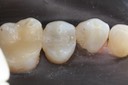

Alan Chinn #28 finish